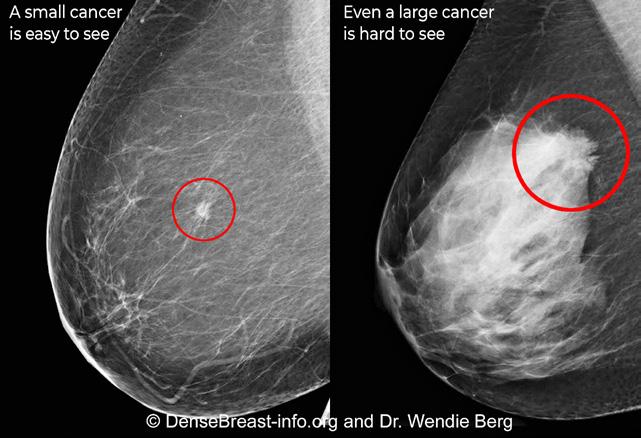

How does dense tissue affect my mammogram?

Dense breast tissue is white on a mammogram and fatty tissue appears dark gray (see image). Unfortunately, cancers also display as white on a mammogram. If there is a lot of dense tissue on a mammogram, a cancer can be “hidden” among the dense tissue. This is true even if the mammogram is done with 3D/tomosynthesis.

For women with dense breasts, a “normal,” “negative,” or “benign” mammogram does not necessarily mean cancer is not present. No matter how recent your last mammogram, a lump or any changes in your breast should be brought to the attention of your health provider.